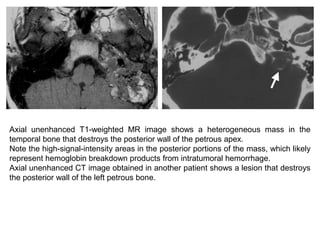

Axial unenhanced T1-weighted MR image shows a heterogeneous mass in the

temporal bone that destroys the posterior wall of the petrous apex.

Note the high-signal-intensity areas in the posterior portions of the mass, which likely

represent hemoglobin breakdown products from intratumoral hemorrhage.

Axial unenhanced CT image obtained in another patient shows a lesion that destroys

the posterior wall of the left petrous bone.